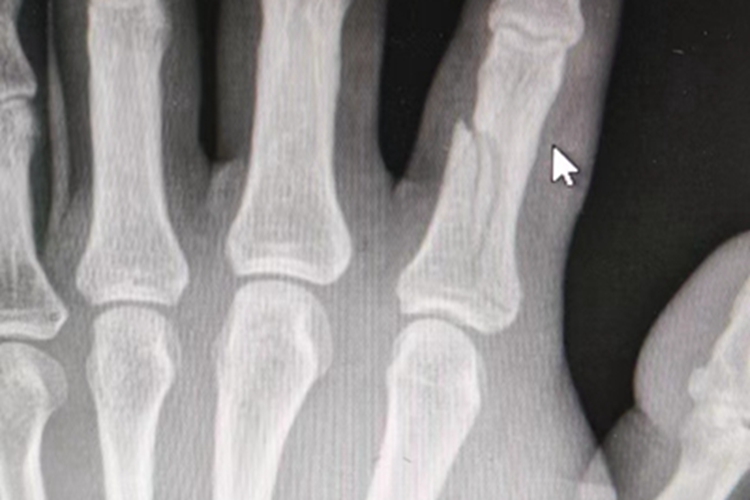

骨折发生在手指部位时,受伤部位的皮肤发红、肿胀,可明显高于周围正常皮肤,同时患者可因疼痛剧烈、肿胀使患肢活动受限。患者在进行影像学检查时,可见局部发生断裂,并有明显的裂纹,断裂面不规整。